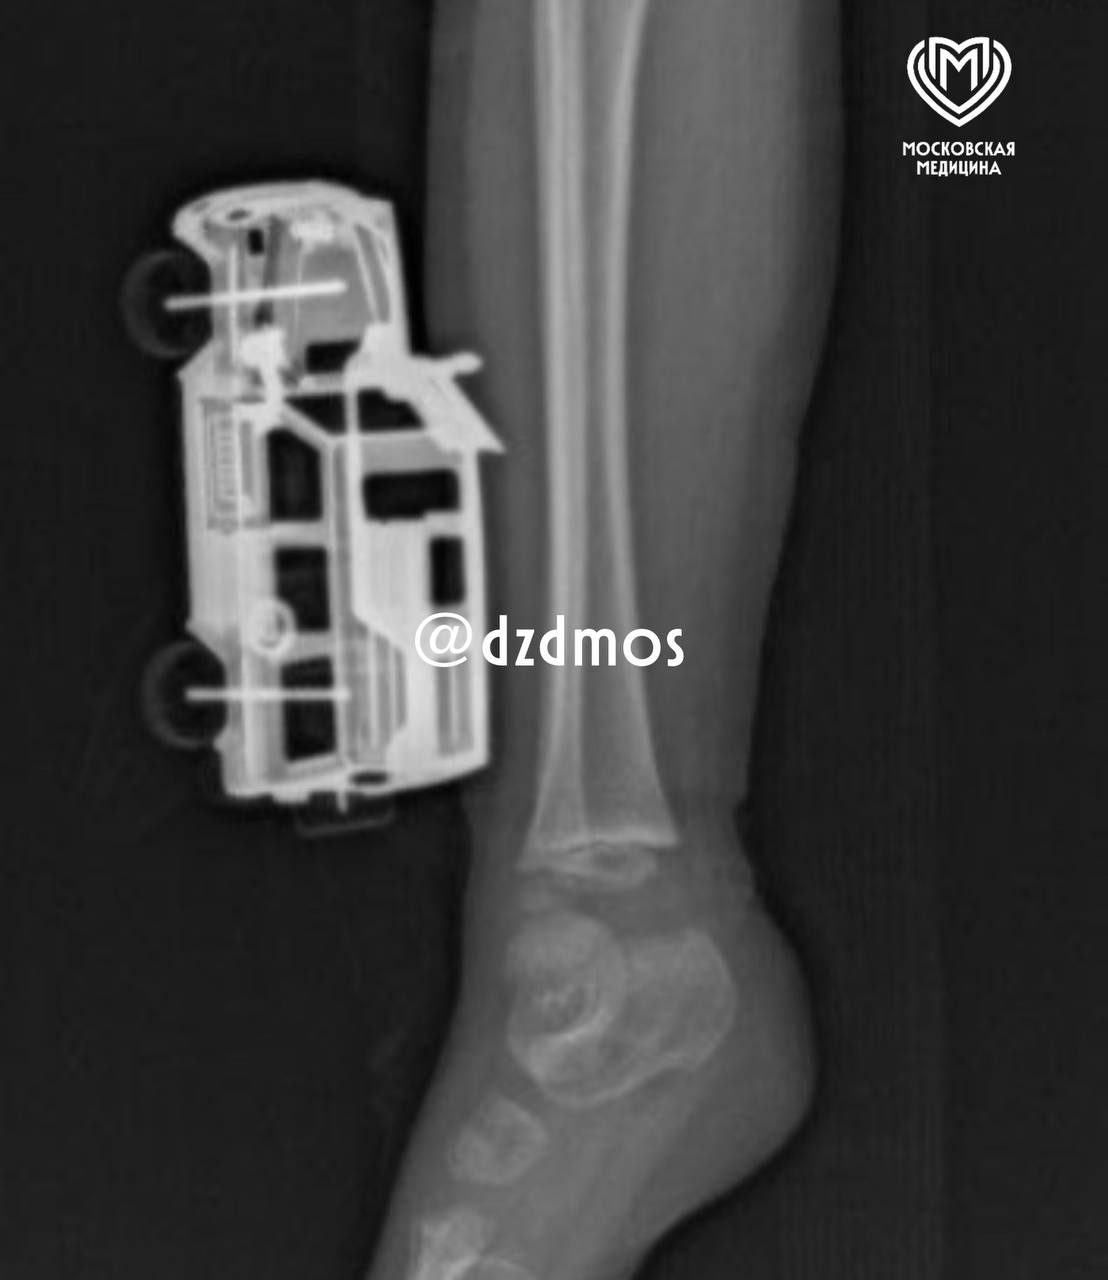

В Москве четырехлетний мальчик упал на игрушечную машинку и оказался в больнице. Об этом сообщает Telegram-канал «Московская медицина».

По словам родителей, ребенок прыгнул с кровати у себя дома и неудачно упал на игрушку правой голенью. Машинка повредила мягкие ткани, ее части вошли глубоко и достигли подкожножировой клетчатки.

Пострадавшего мальчика доставили в больницу, где ему сделали рентген, чтобы исключить повреждение костей. После этого медики удалили игрушку и провели хирургическую обработку образовавшейся на ноге ребенка раны. Через сутки малолетнего пациента уже выписали домой.